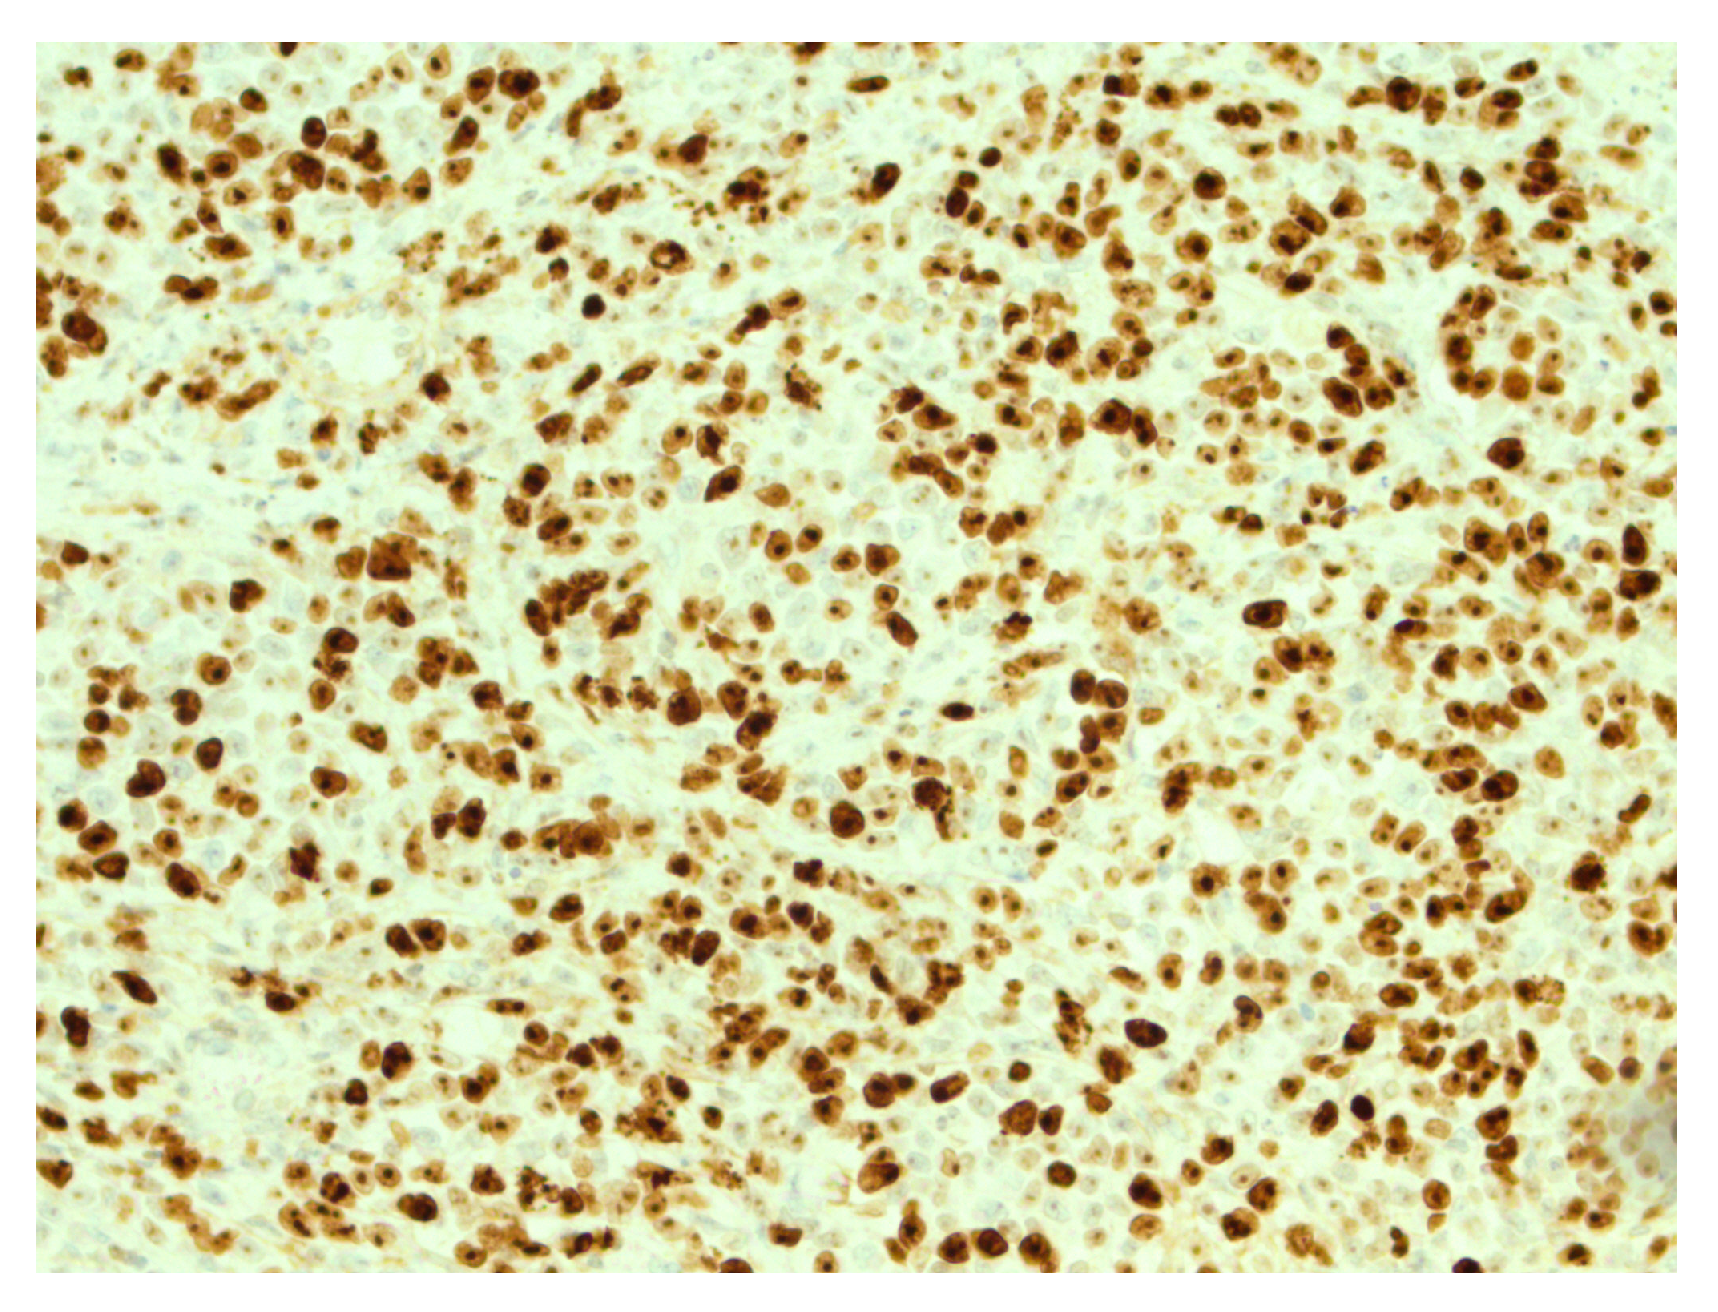

Figure 6.

Retained expression of INI-1 (SMARCB1) in tumor cells, IHC, ×200.